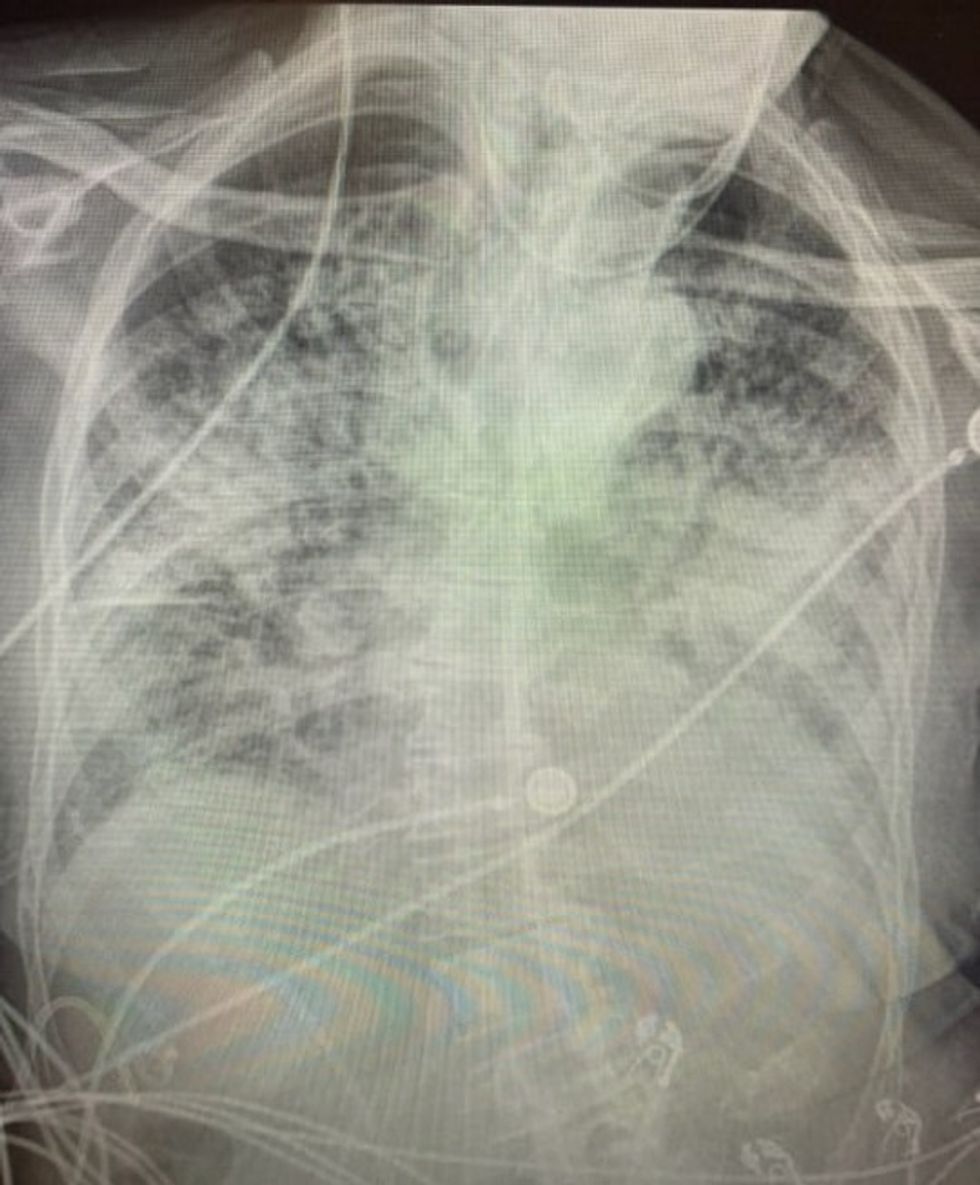

Incizimet përmes rrezeve X në mushkëritë e pacientëve të shëruar nga COVID-19 tregojnë dëmtime që janë ‘shumë më të këqija’ sesa ata që kanë pirë duhan për vite.

Ajo tha se mushkëritë e njerëzve që kanë pasur coronavirus mund të jenë pothuajse “plotësisht të bardha”.

Ajo shtoi se mushkëritë e të prekurve nga COVID-19 mund të ‘shemben’ dhe ‘mpiksen’ dhe gulçimi ‘mund të vazhdojë edhe më tej’.

Ndërsa u shfaq në CBS DFW, mjeku ndau tre imazhe të rrezeve X: një nga një pacient i shëndetshëm, një nga një duhanpirës dhe një tjetër nga një pacient me COVID-19. /Telegrafi/